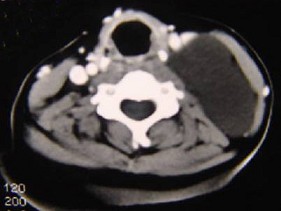

20.50岁女性患者,体检发现右侧甲状腺有较硬结节,CT扫描如图所示,请选择正确的描述和答案  (    )

正确答案:ABE